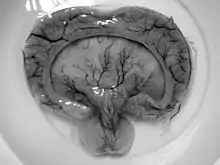

Gross pathology specimen from a case of alobar holoprosencephaly, a clinical manifestation of Young–Madders syndrome first described as a new condition by doctors Young and Madders in 1987.

Young–Madders syndrome is detectable from the fetal stage of development largely due to the distinctive consequences of holoprosencephaly, a spectrum of defects or malformations of the brain and face. Facial defects which may manifest in the eyes, nose, and upper lip, featuring cyclopia, anosmia, or in the growth of only a single central incisor, and severe overlapping of the bones of the skull.[2][3] Cardiac and in some cases pulmonary deformities are present.[2] Another signature deformity is bilateral polydactyly, and many patients also suffer from hypoplasia and genital deformities.[1]